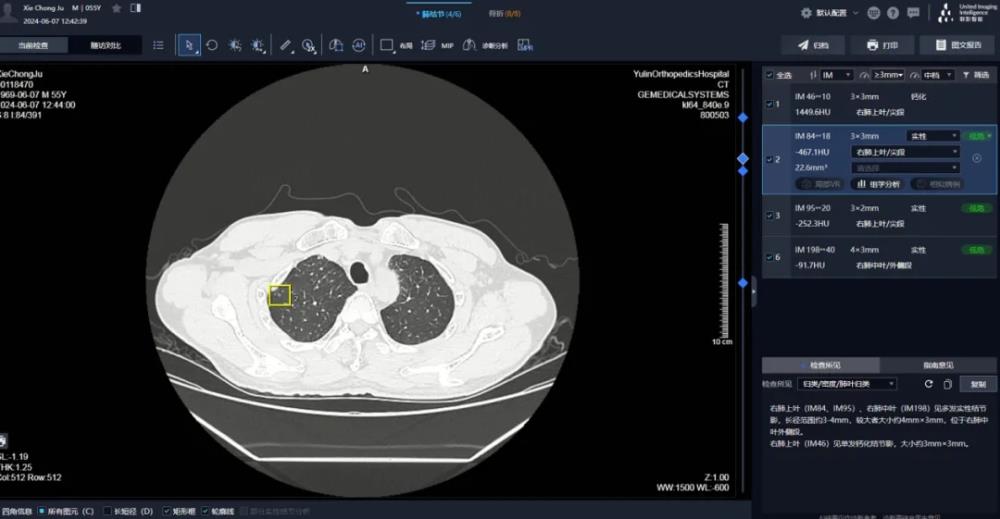

▲AI在肺结节诊断中的应用

AI影像质量检测辅助系统

◆(一)AI影像质量检测辅助系统具备以下功能:

1.自动识别影像质量问题

系统可自动识别影像中存在的伪影、噪声、分辨率不足等问题,并进行分类和标注,提醒技术人员及时处理。

2.智能评估影像质量

系统可根据预设的质量标准,对影像质量进行智能评估,并生成评估报告,为影像质量控制提供依据。

3.辅助优化影像采集参数